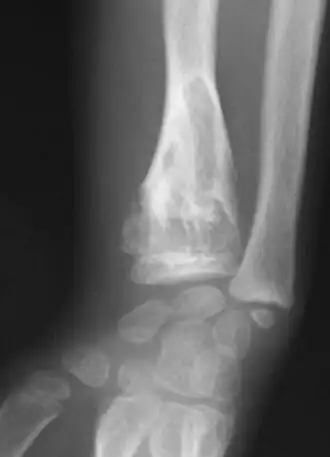

Exemple d'expression de la maladie d'Ollier, chez une fillette de 7 ans (radius)

Les premières manifestations de la maladie apparaissent en général durant la petite enfance du fait d'un développement perturbé de l'os par la croissance d'enchondromes multiples entraînant déformations, déviations axiales et différences de longueur entre les membres. Les tuméfactions osseuses se présentent radiologiquement comme des lacunes claires arrondies, finissant par se calcifier[7]. La pose du diagnostic se fait par un examen radiologique.